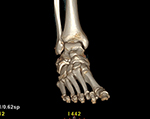

If you are a candidate for an ankle replacement, we will then obtain a CT (computed tomography) scan with multiple views creating a 3D assessment of your unique anatomy.

Your knee will be included in the CT scan to further improve alignment.

The CT scan allows us to create the patient-specific parameters used to plan and perform your surgical procedure with enhanced accuracy.